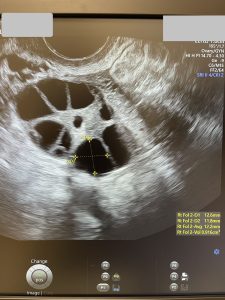

· O rezervă ovariană incredibilă (pentru aproape 42 de ani!): AMH de 4,1 ng/ml în urmă cu 2 ani; la ecografie, un AFC de 33!

La momentul în care scriu aceste rânduri, am făcut deja și a treia stimulare, am obținut 16 ovocite și 6 blastociști. Toți au fost testați PGT-A și așteptăm să vină rezultatul testării…